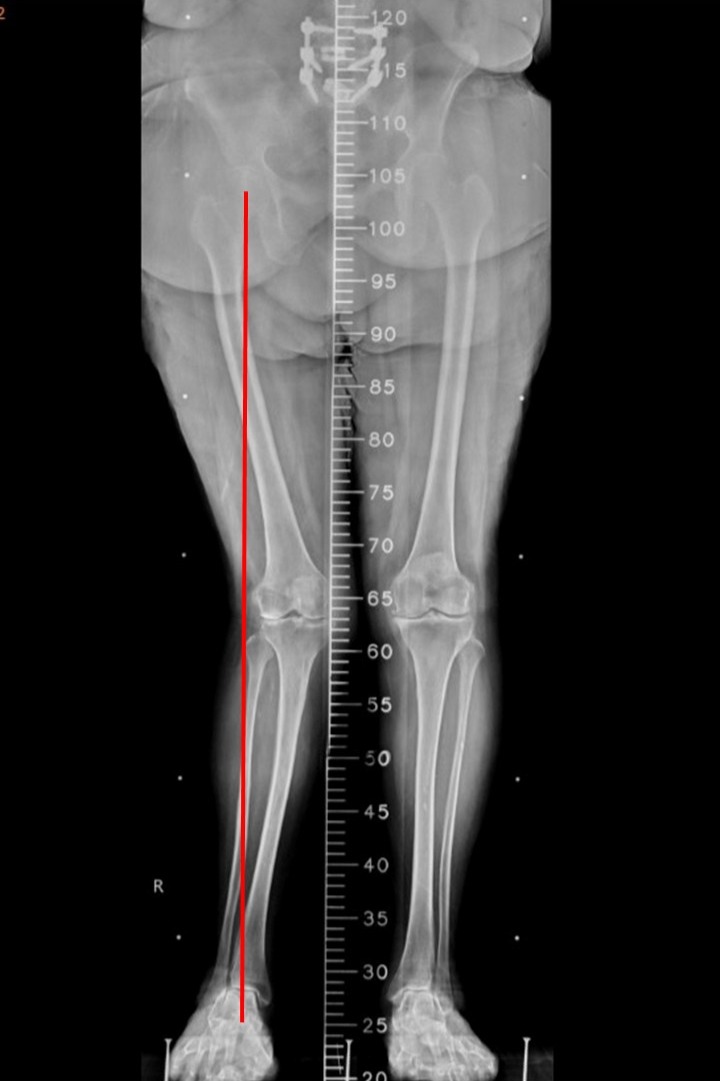

圖說:術前X光顯示,右膝關節軟骨幾乎完全磨耗,膝關節軸向明顯變形,屬於嚴重退化性關節炎。術前測量顯示,右下肢受力軸線已完全偏離膝關節的承載面,形成明顯的外翻膝。

圖說:機器人手臂膝關節置換手術系統輔助右膝全人工關節置換手術後,術後X光顯示關節變形獲得明顯矯正,右下肢的受力軸線重新回歸膝關節承載面。此外,術前站立時的骨盆傾斜,也在術後獲得間接矯正。